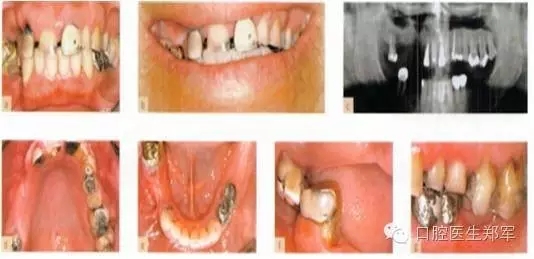

圖片5到12案例介紹了部分牙列缺損導致的功能缺失和美學受損。

形態(tài)缺陷的診斷包括:牙列缺損、后牙支撐減少、輕度到中度的垂直距離喪失,美學和功能障礙,以及不良修復體。

口腔疾病和功能障礙包括:繼發(fā)齲、可復性關節(jié)盤移位、繼發(fā)創(chuàng)傷、臨床附著喪失≥5mm超過30%的位點的嚴重慢性牙周炎。

圖5 a-g 局部缺牙、美學缺陷、牙列缺損、后牙牙合支撐喪失、部分牙段過度萌出、咬合垂直距離中度喪失(圖片由Dr. 0 Ghelfan提供) |